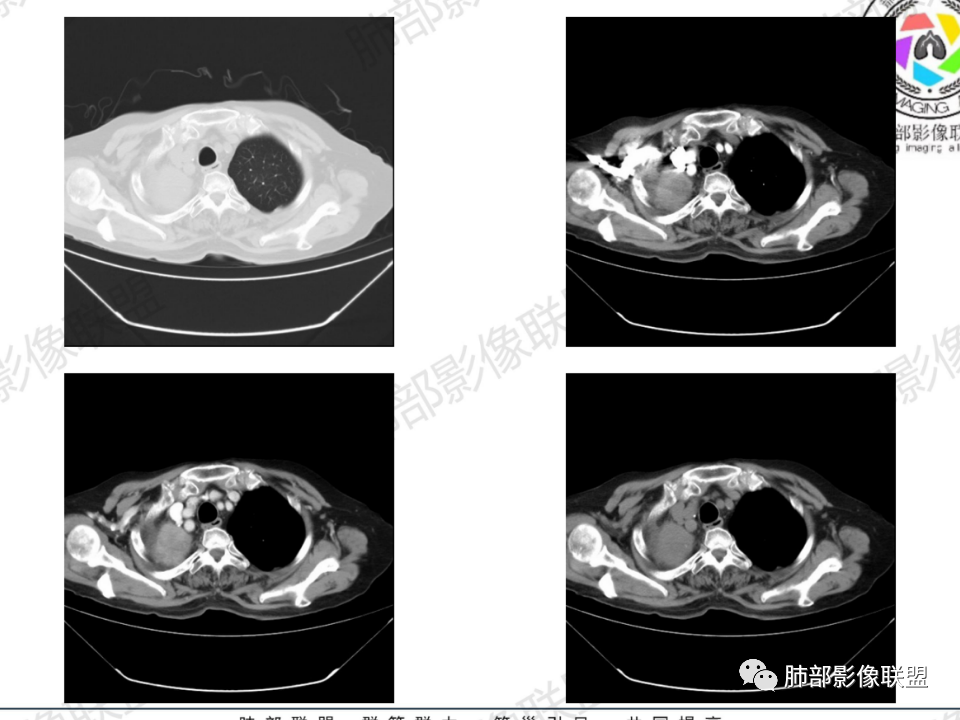

那个人:老年女性,亚急性病程,咳嗽发热。有垂体前叶功能减退,目前激素替代治疗,长期激素,量小,不知道累积量,没有目前激素水平指标。既往有淋巴结结核病史。肿瘤标记物Ca125升高。血沉升高,C反应蛋白轻度异常。影像,右肺上叶靠近肺门团块影,右肺门淋巴结钙化肿大,支气管狭窄,局部增厚,团块影外朝内改变,强化明显,血管破坏不明显,有粘液。和纵隔胸膜分界清楚,周围肺组织有斑片渗出影,右侧胸腔积液,考虑炎性?结核?支气管镜检查除外恶性飞鹰行动:老年患者,影像表现 右肺上叶占位性病变,边界清楚,有分叶征,内见细小钙化,右肺上叶支气管截断,增强病灶不均匀强化,病灶内有条状坏死区(扩张的支气管?),纵膈内未见增大淋巴结,考虑炎性病变,结核可能。一切∮随缘:右肺上叶实性肿块形态不规则,呈三角形,边缘分叶,边界伴有磨玻璃影,近段支气管未见明显显示,可能堵塞,病变平扫密度均匀,增强后可见低密度坏死无强化,周围略强化,右肺下叶散在结节。心包积液,及右侧胸腔积液,临床:有低热,低蛋白血症,肿瘤标记物高,考虑恶性:腺癌,神经内分泌癌(强化偏弱了),淋巴瘤,鉴别:结核红星:老年女性患者右肺上叶,肺门上区 分叶状肿块 ,右肺上叶支气管显示不清,增强扫描肿块,中等程度强化可见小斑片状坏死区,病灶内部可见斑点状钙化灶,病灶周围可见斑片状及小斑点状影,纵膈淋巴结增大,其他区域,胸膜下可见斑点状钙化。考虑肉芽肿性病变,结核的可能性大。老年患者最排除肿瘤性病变腺癌。土娃:右上肺不规则肿块影,边缘分叶,边界磨玻璃影欠清,病灶分叉状,内见点状钙化影及坏死灶,支气管堵塞,病灶增强强化不明显。考虑瘤样结核,鉴别淋巴瘤。张小兵:老年女性,亚急性病程,右肺上叶见不规则肿块,边缘平直凹陷为主,周围GGO边界不清,内见点状钙化及坏死灶,增强持续性渐进强化,右侧少量胸腔积液,双肺门及纵隔肿大淋巴结伴钙化,综合考虑慢性炎症。saf:老年患者,影像表现 右肺上叶占位性病变,边界清楚,有分叶征,增强病灶明显不均匀强化,纵膈内未见增大淋巴结,考虑炎性病变,结核可能。小兜:老年女性,咳嗽喘息一月,发热三天,肿瘤标志物升高,长期激素替代治疗。CT示右肺上叶近肺门不规则实变影,周围伴磨玻璃影,增强持续性渐进强化,内部血管破坏不厉害,内部可见多发条形低密度灶,右侧胸腔可见少量积液,双肺门及纵隔可见钙化淋巴结,考虑为炎性病变,结核可能玫:女,79咳嗽,喘息一月,发热三天入院,右肺上叶不规则形软组织密度肿块影,边界清晰,边缘见分叶及细短毛刺,病灶内见点状钙化影及稍低密度区,病灶边缘呈磨玻璃样改变,增强扫描,病灶呈不均匀性强化,考虑炎性病变,鉴别鳞癌。大雄:老年女性,既往诊断淋巴结结核,提示已治愈,近2年服用激素,诱导结核复燃→发热;纵隔肺门淋巴结肿大钙化,压迫支气管,右肺上中下叶支气管均狭窄→喘息咳嗽;尖段支气管受累闭塞→肺不张、支气管粘液栓;累及胸膜,结核性胸膜炎并胸水→右侧胸痛;实验室,血沉快,CA125高,低蛋白,符合;下一步,支气管镜尖段支气管刷检抗酸染色周太狼:老年女性,亚急性病程,肿瘤标志物升高。CT示右肺上叶尖段不规则肿块影,有分叶、收缩,周围伴磨玻璃影,增强渐进强化,内部可见多发条形低密度灶,右侧胸腔及心包少量积液,纵隔内淋巴结稍增大。倾向于恶性病变,肺癌伴阻塞性炎变可能。丽:老年女性,右肺上叶不规则软组织肿块,边缘清晰,内密度不均,可见点状钙化及粘液栓,周围可见片状高密度影,增强后均匀强化,内多发低密度,纵膈多发钙化淋巴结,考虑结核可能大,建议结合支气管镜检查除外肿瘤宇宙:右胸廓缩小,右肺上叶团块影及不张,平直边,周围磨玻璃影,纤细胸膜牵拉,上叶尖段支气管堵塞,明显延迟强化,可见支气管粘液栓,两肺门钙化淋巴结,右侧胸水,考性炎性肉芽肿,鉴别腺癌王秀仙:右肺上叶肺门区肿块,上叶支气管开口阻塞,形态不规则,密度不均,内可见支气管粘液栓及多发小灶性坏死,周围磨玻璃影边缘模糊,渐进强化,右侧胸腔积液、胸膜钙化,考虑炎性肉芽肿性病变,慢性炎症。鉴别鳞癌,结核。刘丹:老年女性,右肺上叶肿块伴钙化,右肺上叶支气管截断,增强后均匀强化,周边可见点片状模糊影,右侧胸腔积液,右肺门淋巴结增大,考虑占位并阻塞性炎症,肿瘤?结核?建议纤支镜检查。小飞:右肺上叶纵隔旁软组织肿块,边缘深分叶、长毛刺及毛刷样短毛刺,边缘磨玻璃影,磨玻璃边界模糊,支气管截断,平扫密度不均,可见点状钙化,增强不均匀明显强化,心影增大,心包积液,右侧胸腔积液,考虑恶性肿瘤,腺癌?秦化君:右肺上叶不规则分叶软组织密度肿块,边缘清晰,胸膜牵拉,周围花花草草,上叶尖段支气管阻塞,内可见点状钙化,增强后密度不均可见支气管粘液栓及坏死区,内见血管分枝。中间段及中叶,下叶支气管狭窄,壁见钙化。右肺门淋巴结肿大,右侧胸腔积液,心包粘连肥厚。考虑1右上肺恶性病变,鳞癌?2右肺多叶段支气管狭窄,考虑支气管内膜结核?3胸腔积液及肺门淋巴结肿大,转移?风儿:老年女性,右肺上叶肿块,形态不规则,外围大内带小,边缘分叶膨隆平直及毛糙,密度不均,内见支气管粘液栓及多发小灶性坏死,坏死边缘清晰 ,渐进强化,上叶尖段支气管阻塞,叶支气管壁有局限性增厚,邻近胸膜腔微积液;纵隔及双肺门淋巴结肿大,部分钙化,右侧胸腔积液、心包积液、胸膜钙化,考虑炎性,肉芽肿性结核可能性大。鉴别鳞癌,女性及血供均不支持;腺癌,坏死边界太清晰。流心明智:老年女性,79岁,咳嗽、气短1月,发热3天。胸CT:右肺上叶见不规则肿块,边缘有膨隆、有平直凹陷,周围GGO边界不清,病灶内见点状钙化、粘液栓,尖段支气管未见,增强持续性渐进强化,右侧少量胸腔积液,双肺门及纵隔肿大淋巴结伴钙化,肺动脉增粗。考虑:右上叶尖段堵塞并慢性炎症,支气管TB并结石?鉴别Ca

临床信息:老年女性,亚急性病程,咳嗽发热。有激素使用史。既往有淋巴结结核病史。肿瘤标记物Ca125升高。血沉升高,C反应蛋白轻度异常。 影像所见:右侧胸廓相对狭小,右肺上叶不规则团块影贴附纵隔旁,轻度分叶,整体密度较均匀,偶见钙点。

相应上叶尖端及前段支气管开口未能追踪(阻塞),开口处见钙化。病灶渐进性强化,并衬托出较完整尖段及前段含液支气管影。支气管开口区域未见异常高密度强化(如类癌等)及相对乏血供区(如鳞癌)。病灶区未见液化坏死。右上纵隔及胸廓入口区未见病灶胸膜外突破(栽赃)。

纵隔及双肺门见钙化淋巴结。心包积液,右侧胸腔积液(提示存在活动新病灶)。双侧胸膜下见多发斑点状钙化,胸廓变形(提示存在结核基础病变可能)。 诊断意见:综上,右肺上叶块状影更符合继发性肺结核。 最后小结:既往诊断淋巴结结核,提示已治愈。近2年服用激素,可疑诱导结核复燃,也可引起发热。纵隔肺门淋巴结肿大钙化,压迫支气管,右肺上中下叶支气管均狭窄,所以引起喘息咳嗽。尖段支气管受累闭塞,导致肺不张、支气管粘液栓,出现条状无强化区。病变累及胸膜,导致结核性胸膜炎并胸水,引起右侧胸痛。实验室检查血沉快,CA125高,低蛋白,均符合结核。下一步,建议支气管镜尖段支气管刷检并抗酸染色。(本段摘自於雄老师精彩发言)